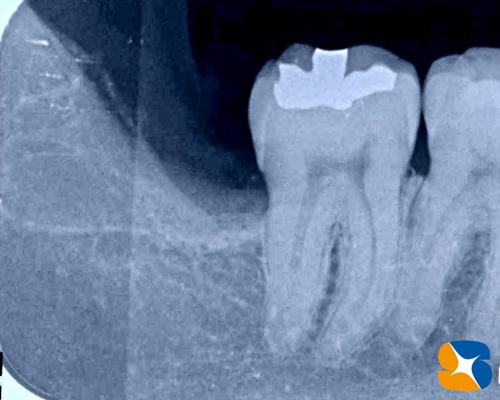

レントゲンからも大きな虫歯を確認。本日、昼休み中にインプラント手術があります。それが終わり次第抜歯を行うことにしました。

歯の上半分が虫歯のため、崩壊していましたので難しい抜歯になりましたが、無事に終えることができました。